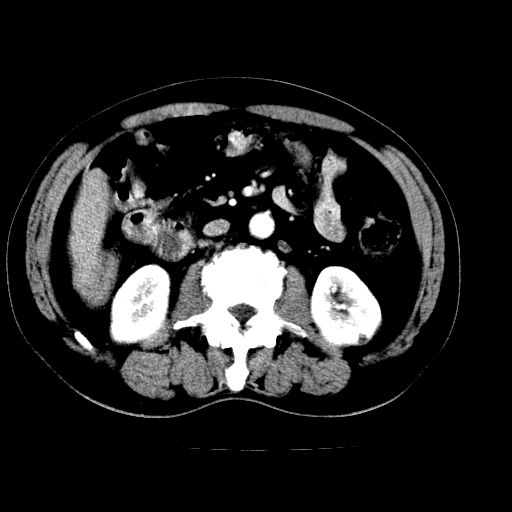

男,66岁,上腹部不适、黄染一周。彩超示:肝左叶占位,肝内胆管扩张,胆总管扩张,胆总管占位?

肝左叶不规则软组织肿块影,边缘不规整邻近肝实质受累分界不清;肝内胆管(左叶)明显扩张成“软藤状”,诊断:肝左叶胆管细胞癌。

左叶胆管细胞癌累及胆总管,门脉左支受侵,慢性胆囊炎胆结石,左肾小囊肿

胆囊缩小,其内胆汁浓缩,也提示梗阻部位应该位于胆囊管起始部以上或是胆囊管受累及,支持肝外胆管癌。